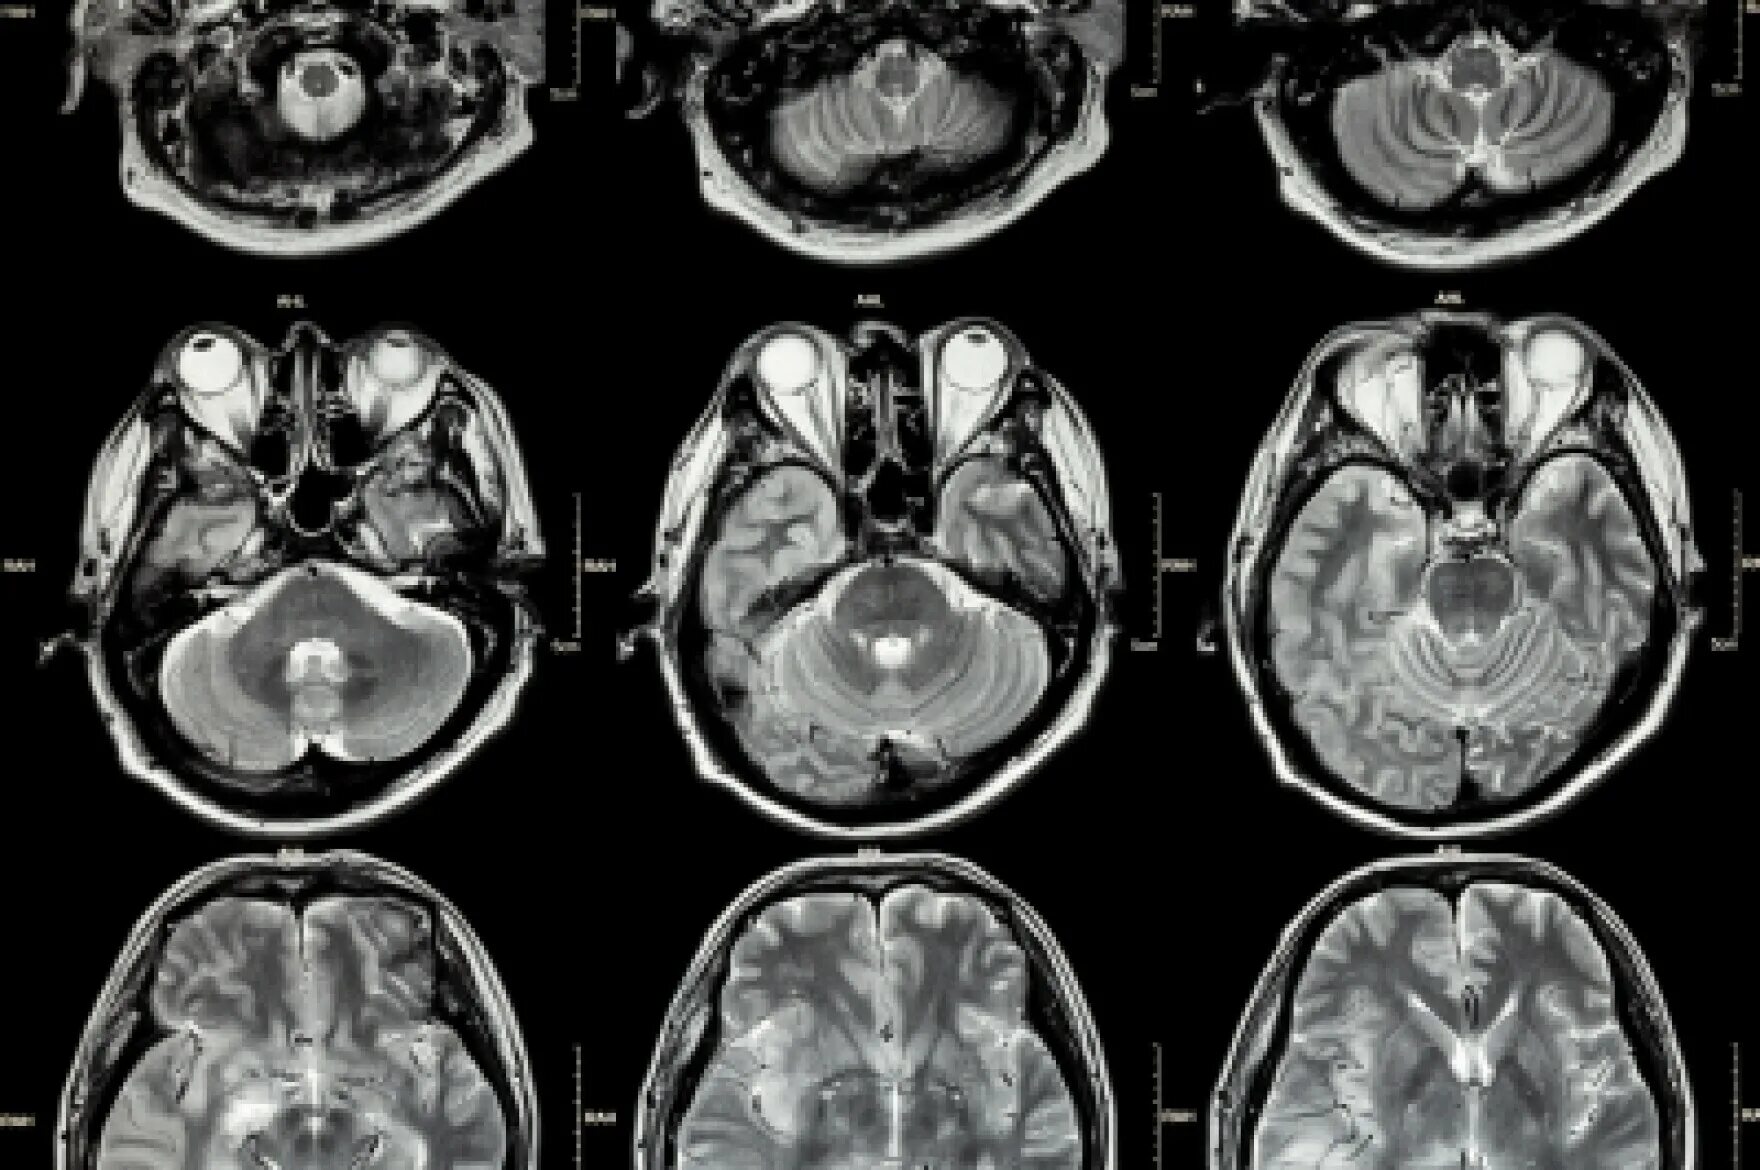

Данные мрт